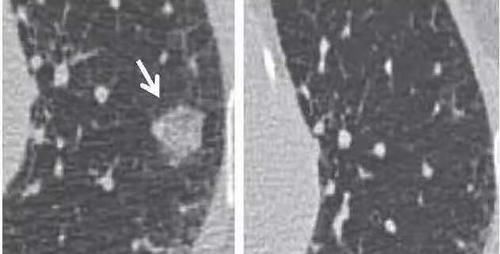

再看第二个病例,如下图:

文章插图

患者第一次检查发现左肺结节(上图左侧),对于这种结节,我们同样也没有办法确定性质,但是结节有点大,于是建议患者三个月复查,三个月患者再次做了胸部CT(上图右侧),结果发现原来的结节消失不见了。那么对于这种消失不见的结节,我们可以很确定地说它是良性的结节。